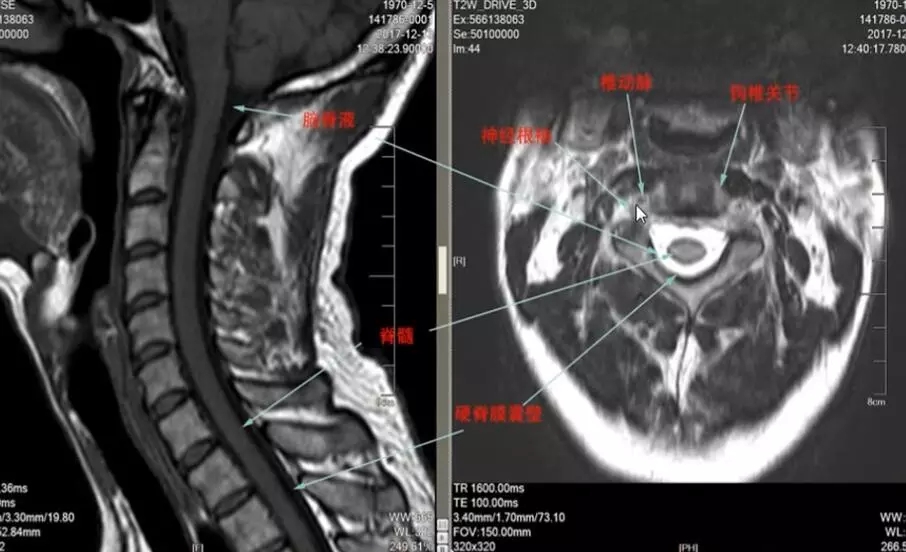

扫颈椎mr经常可以看到椎动脉

根性颈椎病,椎间盘脱出

这是一个椎间盘突出引起的神经根型颈椎病,我们在矢状面可以看到这里有突出的椎间盘,在横断面也可以看到突出的椎间盘压迫了神经根,治疗原则主要是前路,摘取致压物,还有进行椎间融合,但目前也有经椎间孔镜通后路进行致压物的摘取。根性颈椎病的预后,如果是单纯的椎间不稳,椎间盘突出或者脱出的,预后比较好,如果是由于钩椎关节增生导致根袖黏连,这样的病例症状会发生延续,预后较差。如果是广泛性的骨质增生造成的压迫,发生了变性,预后则更差